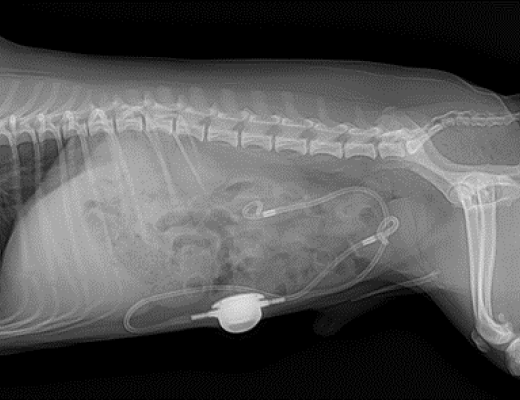

2-1 2-2

요관 내에 결석 여러 개 관찰된 모습

피하요관우회술

Subcutaneous Ureteral Bypass, SUB

요관 폐색의 경우 폐색으로 인해 신우(신장의 깔때기) 부위가 확장되게 되면 해당 부분과 방광을 연결하는 피하요관우회술(Subcutaneous Ureteral Bypass, SUB)이 가장 일반적인 수술 방법입니다.

SUB 수술법이 개발되기 전에는 요관 내 결석을 직접 제거하는 수술 혹은 요관 내 스텐트를 장착하는 수술이 진행되었으나, 이러한 치료 방법들은 협착에 의한 합병증 가능성이 높고, 스텐트의 제거 교체 등이 불가능하여, 최근에는 지양되고 있습니다.

요관 폐색으로 인해 SUB 수술적 치료 진행

피하요관우회술이란?

신장과 방광에 각각 카테터(관)을 삽입하고, 이 두 카테터를 피하(피부 아래)에 위치한 작은 포트(장치)로 연결합니다. 이 포트를 통해 신장의 소변이 방광으로 직접 유입되며, 막힌 요관을 우회하게 됩니다.

전통적인 요관 수술 방법에 비해 합병증과 사망률이 낮고, 수술 후 관리가 비교적 간편합니다. 특히 수술 후 주기적으로 포트를 통해 소변 배출 상태를 확인하거나, 소변 채취 및 세척이 가능하여 장기 관리면에서도 기존 수술 방법과 비교하여 우수한 수술 방법입니다.